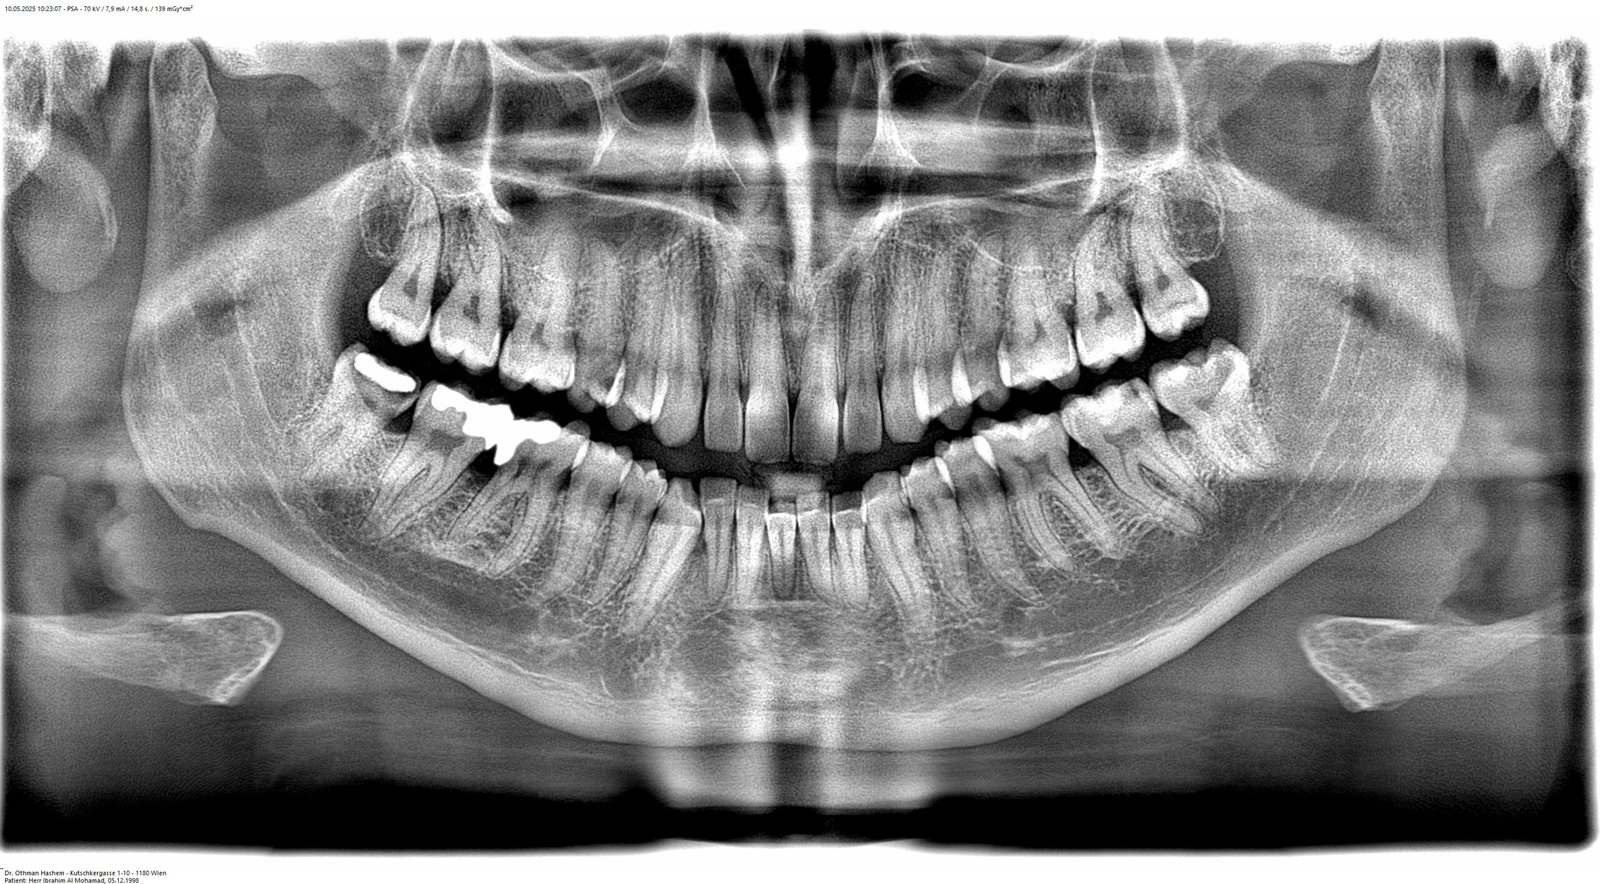

Digitales 3D-Röntgen (DVT)

Präzise 3D-Diagnostik für Implantate und komplexe Behandlungen

Unser modernes DVT-Gerät ermöglicht dreidimensionale Aufnahmen des Kiefers mit

minimaler Strahlenbelastung. Die präzisen 3D-Bilder sind Grundlage für

implantologische Behandlungen, Wurzelkanaltherapien und die Planung komplexer

zahnärztlicher Eingriffe.

Geringste Strahlenbelastung im Vergleich zu herkömmlichen Röntgengeräten

Hochpräzise 3D-Bilder für exakte Behandlungsplanung

Schnelle Aufnahme in nur wenigen Sekunden

Komfortable und angstfreie Untersuchung für Patienten